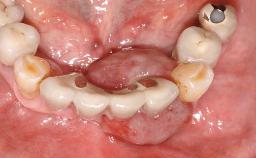

A 65-year-old female patient was referred to the periodontist for assessment and management of implant site 12. Implant 12 had been placed ten years previously and restored with a cemented single crown. The patient was a non-smoker in good general and periodontal health. On examination there were 7 mm probing depths at implant 12 with suppuration and bleeding on probing. The patient was aware of the presence of pus but had no discomfort. A periapical radiograph showed marginal bone loss to approximately the third thread of the implant. Previous radiographs obtained from the referring clinician indicated that there had been progressive bone loss since the implant was restored. A diagnosis of periimplantitis was made.